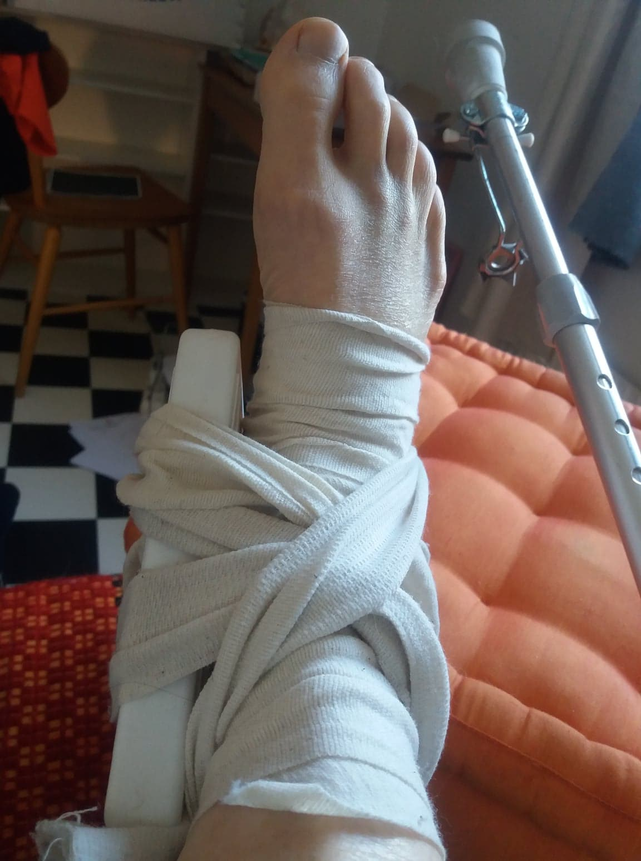

Långfredag i skärgården. Kraftig vrickning. 6-8 veckors läkning säger läkaren efter röntgen. Avslitna ligament och en lös benflisa.

1 juni är om sex veckor och då skall bygget vara klart på Bergmancenter. .

Det är inte bra. Jag kan inte stödja på foten, hur skalll jag överhuvudtaget ta mig till Fårö? Bo i husvagn, cykla och handla mat OCH göra utställningen klar????

Finns en improviserad förenklad plan B?

Ostiopatbehandling, högläge, binda, kylklampar hopp med kryckor. Efter en vecka kan jag knyta på kängorna och promenera.